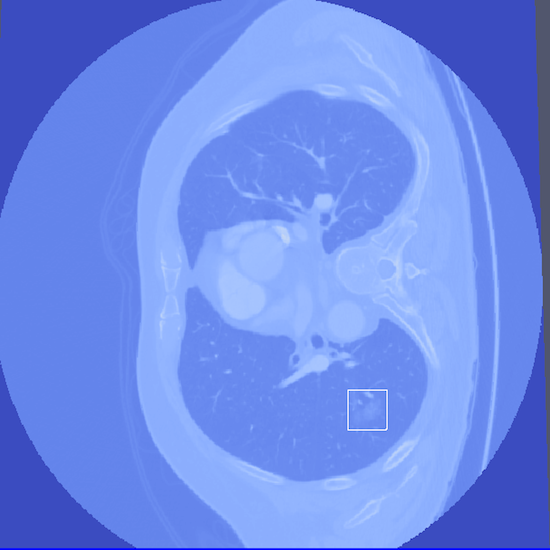

Bottom Row: Examples of lung nodule detections.

- Abstract: An exploration of whether conventional detection methods of lung cancers in low dose spiral CT scan could be improved using curvature features. In general, a large source of inaccuracy in detection rates can be attributed to irrelevant anatomical structures such as blood vessels. Often these irrelevant anatomical structures have different shape characteristics from lung nodules. For example lung nodules tend to appear bloblike as oppose to blood vessels, which appear cylindrical, or organ walls, which appear planelike. These curvature features were determined using eigenanalysis of the local second order image Hessian of each voxel, where the principal values are indicative of the local shape and provide more information than analysis performed on first derivatives alone.

- Method Overview: In each CT scan, the internal 3D lung volume was isolated using standard thresholding of pressurevalues ranges associated with lung parenchyma. The remaining voxels were conjoined using a connected components method, implemented through a union-find method, with small and isolated components removed. The remaining gaps were filled in using a standard 3D image closure method. First and second order partial derivatives were computed using Deriche filters, chosen for their stability and suitability in medical image scans. Then, for each of the voxels in the internal volume of the lung the local second order Image Hessian was generated and analyzed for preferred directions using eigenanalysis. This information was then used to weight the contribution of each voxel to standard lung nodule detection methods, to determine if giving stronger weight to voxels with local blob-like shape improved detections results.